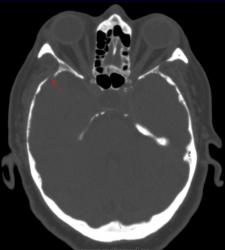

Метастазы в костях основания черепа.

Женщина средних лет с клиникой невралгии тройничного нерва справа. На КТ были выявлены округлые очаги деструкции в костях основания черепа (средней черепной ямки).

Наблюдение Nela.